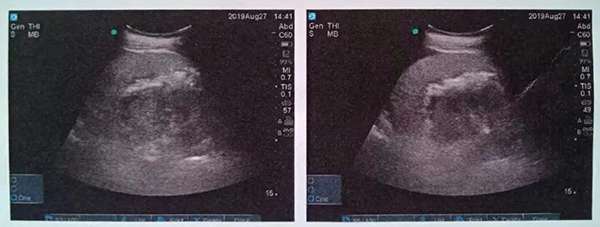

入院后經(jīng)細(xì)致檢查,診斷其為泌尿系結(jié)石,右腎積水,右輸尿管梗阻,30余年前曾在錢糧湖醫(yī)院行闌尾切除術(shù)及腸梗阻手術(shù)。由于患者右腎為重復(fù)腎合并結(jié)石,解剖結(jié)構(gòu)和病情極其復(fù)雜。泌尿外科周旭陽主任組織科室專家進(jìn)行術(shù)前討論,決定在充分抗感染治療的基礎(chǔ)上行經(jīng)皮腎鏡鈥激光碎石術(shù)。

術(shù)中,泌尿外科郭駿博士精心設(shè)計(jì)手術(shù)通道,只在患者體表鉆出兩個0.5厘米的小洞,由于患者右側(cè)上位腎位置高,靠近肝臟和肺下葉,容易出現(xiàn)肝臟和肺的損傷,在B超的引導(dǎo)下精確穿刺腎結(jié)石的最高點(diǎn),逐級擴(kuò)張后建立皮腎通道。這時屢次“惹禍”的腎結(jié)石清楚的顯露在手術(shù)屏幕上,結(jié)石呈淺黃色,表面覆蓋淺褐色的膿苔,然后使用鈥激光將結(jié)石擊碎后取出。歷時一個半小時,結(jié)石全部清除,手術(shù)結(jié)束。